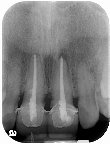

一、拆除假牙,並觀察內部牙齒的損壞情形,進行根管治療,待牙齦腫脹消失後、再進行根管充填(圖三)。

圖三 |